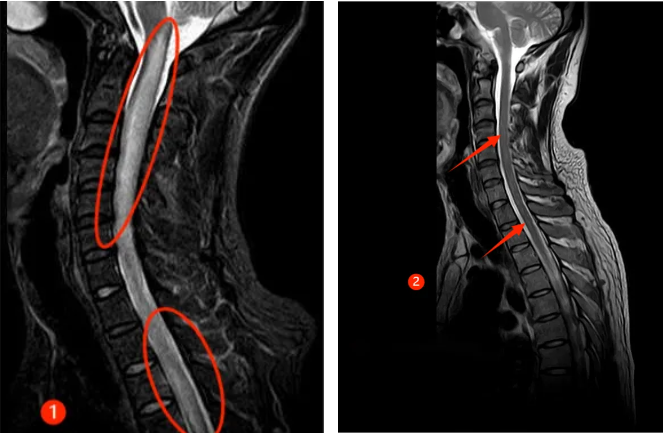

半年前,30来岁的谭先生突然出现颈肩部疼痛不适及肢体麻木,此后短短数天迅速出现四肢瘫痪及大小便失禁,生活不能自理。正值风华正茂的年纪,谭先生一时无法接受,心急如焚的父母带着吓坏了的谭先生来郑州大学第五附属医院就诊,入住神经内科二病区。入科时患者已四肢全瘫,紧急完善相关检查,发现患者脑干、颈髓、胸髓、腰髓广泛病变(见图①),随后完善腰穿及相关抗体检查,最终确诊为MOGAD。

经过及时的免疫治疗,患者病情逐渐好转,出院时患者已能下床行走,再次拾起对生活的信心,复查磁共振,患者脑干、颈髓、胸髓、腰髓的病变已明显好转(见下图②)。半年后随访,患者已恢复正常的生活,预后非常好。